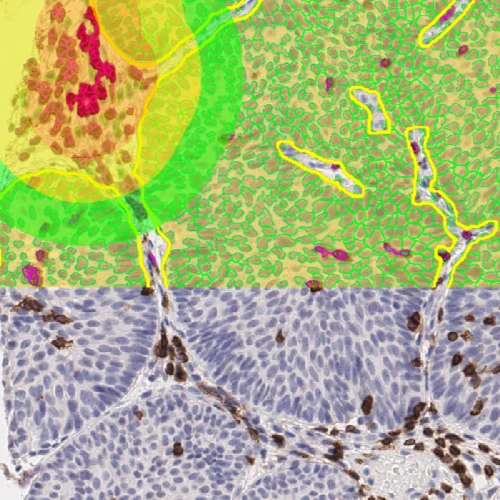

These metabolic shifts influence cellular structure, alter tissue organization, and leave morphological footprints that can be directly observed under a microscope. These changes are usually best visualized using various histological stains, such as hematoxylin and eosin (H&E) staining, or marker-specific, such as immunohistochemical (IHC) staining using specific antibodies.

When brightfield imaging is used in conjunction with the precision of image analysis, researchers can uncover both the form and function of metabolism changes in situ. This integration, defined as brightfield image analysis, reveals not just what metabolic changes are occurring, but exactly where and how they unfold within the native tissue environment.

Brightfield image analysis transfers these structural transformations in actual numbers. Image analysis of images acquired from IHC-stained tissues also enhances data reliability through quantifying subtle expression differences that might be overlooked.

Brightfield image analysis captures the spatial distribution of these stains, mapping metabolic activity across tissue regions. This spatial understanding becomes more powerful with numerical data, which quantifies staining intensity, localization, and variability.

To fully characterize metabolic reprogramming, it's essential to move beyond morphology and directly observe the molecules at its core. IHC allows the visualization of enzymes and transporters including GLUT1, LDHA, CPT1A, and FASN. These markers play defining roles in metabolic pathways including glycolysis, lipogenesis, and fatty acid oxidation.

The combined analysis of IHC data and structural context allows researchers to assess expression levels within distinct tissue regions and compare metabolic profiles across experimental conditions.